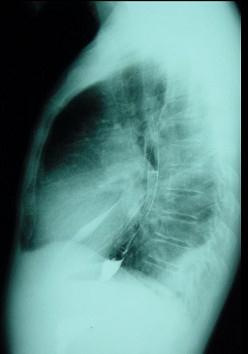

对如下心脏左侧位片描述正确的是 ( )A、正常心脏B、以上均错C、右心房增大D、右心室增大E、左心房Ⅰ度增大

选项 A、正常心脏 B、以上均错 C、右心房增大 D、右心室增大 E、左心房Ⅰ度增大

答案 E